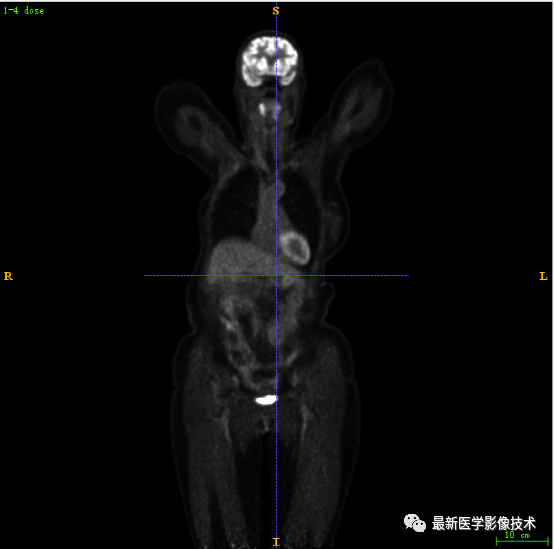

7.2、低剂量4重建结果

第一张是低剂量4的PET图像,第二张是full剂量PET图像,第三张是网络重建的PET图像。